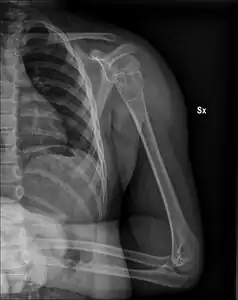

X-ray: Simple bone cyst in left upper arm of 13 year old | |

- Unprovoked break in the long bone of the upper arm,, with "fallen leaf" sign.